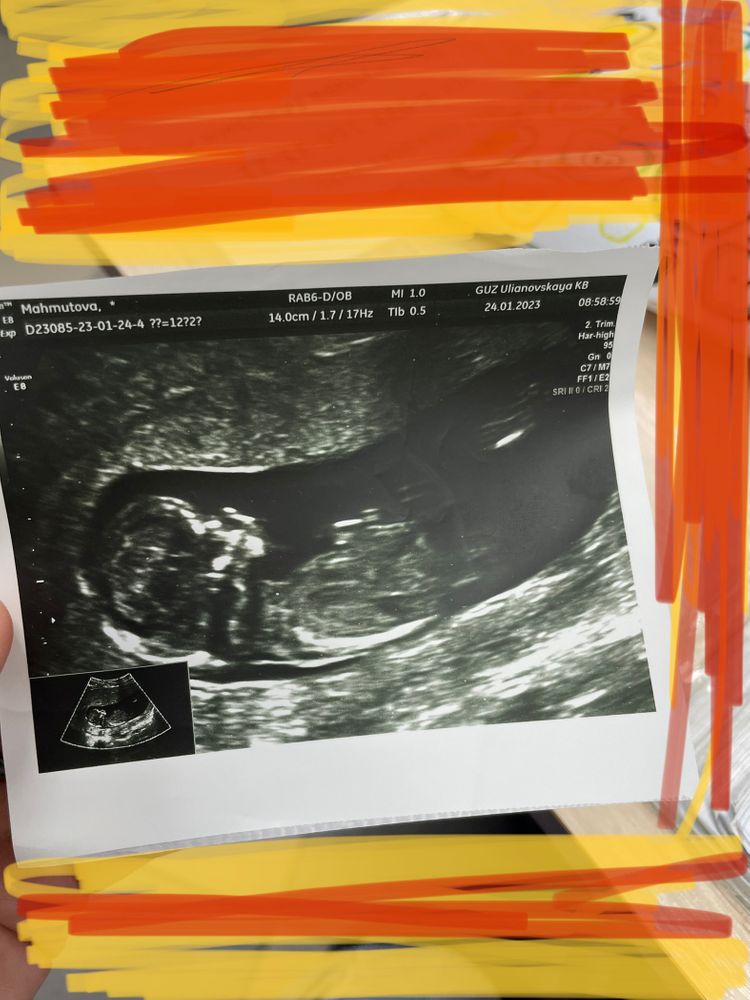

На первом фото половой бугорок паралельно расположен,не под углом, девочка, наверное.

Алина, там недель 13 на фото? На этом сроке пол в этом ракурсе не смотрят, т.к. половых органов еще нет как таковых, а половой бугорок торчит у всех, и у мальчиков, и у девочек. Но это все равно все не точно пока, точно пол может увидеть с 15-16 недель.

Чашка утреннего кофе, да, 13 недель , врач на 3 фото сказал торчит как у пацана) но я не верю)

кажется мальчик....

у девочки прям отчетливая петелька... на последнем фото из-за стрелки плохо видно